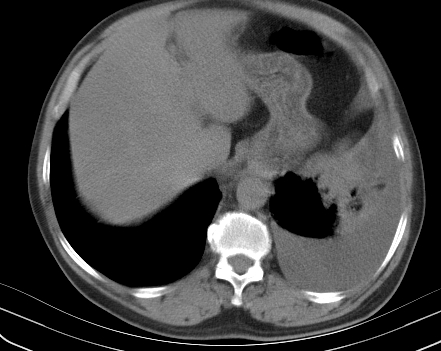

以下是引用老爱克斯新网客在2008-7-31 6:30:00的发言:[br]左肺上叶大片状病灶,左肺上叶支气管狭窄呈鼠尾状,左肺门增大,纵隔内见肿大淋巴结,左侧胸腔积液,余肺清晰。左肺中心型肺癌淋巴结转移,

以下是引用zjzjr在2008-7-31 8:45:00的发言:[br]考虑左侧中心性肺癌伴阻塞性肺炎,左肺上叶肺不张,纵隔淋巴结转移;左侧胸腔积液。建议行纤支镜检查。

以下是引用zjb在2008-7-31 6:32:00的发言:[br]左侧中心性肺癌 阻塞性肺炎 肺不张 胸腔积液 建议气管镜

以下是引用sdzyy在2008-7-31 8:47:00的发言:[br]病灶较治疗前有所进展,胸水增多, 左侧中心性肺癌 并 阻塞性肺炎 肺不张 胸腔积液 可能性大; 建议气管镜检查。 [br] [br]